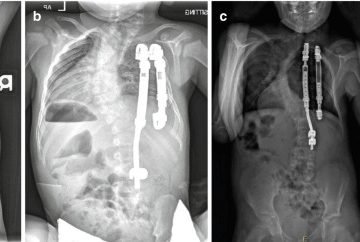

- فیوژن با ابزار فلزی: مهرهها با پیچ و میله به هم متصل و با گرافت استخوانی جوش داده میشوند تا از حرکت جلوگیری کرده و ناپایداری اصلاح شود.

- فیوژن بلندمدت: در موارد شدید گاهی از بالای ستون فقرات و ناحیهی کمری تا لگن انجام میشود.

- استئوتومی: برشهای کنترلشده در استخوان برای اصلاح انحرافات سخت.

- انحراف را بیش از %50 اصلاح کند.

- وضعیت بدن و تعادل را بهبود دهد.